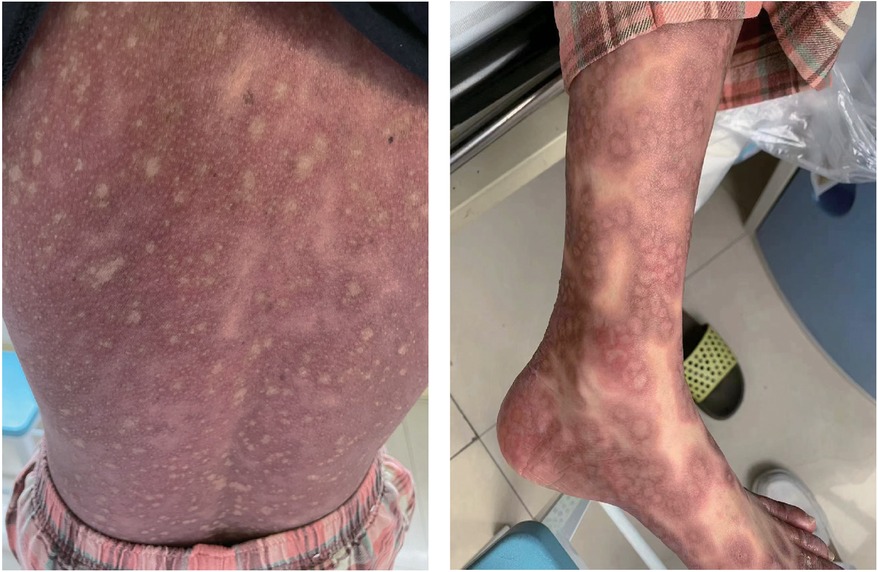

One day after admission, the patient's vital signs were unstable and her blood pressure remained low despite high doses of norepinephrine and m-hydroxyamine. Physical examination revealed scattered red maculae and maculopapules on the trunk and limbs, accompanied by iridoid lesions, blisters, and oral mucosal erosion (Figure 2). Echocardiography examination indicated a significant decrease in Ejection fraction (24%). A review of laboratory tests showed: WBC 6.6 × 109/L, CRP 20.2 mg/L, ALT 225 U/L, LDH 658 U/L, cTnI 20.9 ng/ml, CK 803 U/L, Lactate 6.62 mmol/L, NT-proBNP 6,690 ng/L. Considering the risk of cardiac arrest remains high, endotracheal intubation, V-A ECMO, and emergency coronary angiography were performed. Coronary angiography showed no obvious coronary vessel stenosis (Figure 3). At the same time, we performed extensive hematological tests to determine the cause of the erythema multiforme. Blood cultures were negative for bacteria and fungi. Immunological tests such as antinuclear antibodies, anti-double-stranded DNA antibodies and rheumatoid factors were negative. COVID-19 polymerase chain reaction was negative. HIV, Hep A, B, C and Treponema pallidum serologies were negative. Coxsackie virus, adenovirus, influenza A virus, influenza B virus, human parainfluenza virus, respiratory syncytial virus, Mycoplasma pneumoniae, chlamydia pneumoniae were negative. However, Chemiluminescence showed that herpes simplex virus-1 (HSV-1) was positive. Therefore, we considered that the patient had severe myocarditis and erythema multiforme due to infection with HSV-1 virus. We gave acyclovir needle antiviral and methylprednisolone needle anti-inflammatory. After the initiation of ECMO, the patient's blood pressure significantly increased and gradually stabilized at a systolic blood pressure of 90–168 mmHg and a diastolic blood pressure of 64–112 mmHg. Arterial blood gas analysis showed a significant improvement in acidosis. Therefore, we discontinued all vasoactive medications on the second day following the initiation of ECMO. Four days after the initiation of ECMO, the flow rate was reduced to 1.2 L/min, the patient's blood pressure remained relatively stable, blood gas analysis indicated good tissue perfusion, and follow-up echocardiography showed that the ejection fraction (EF) had recovered to 42%. We concluded that the criteria for ECMO withdrawal had been met, and ECMO was removed four days after its initiation. The day after ECMO was removed, the patient was then scheduled for a cardiac magnetic resonance imagery (CMRI) examination. Cardiac magnetic resonance T2-weighted imaging shows diffuse hypersignal in the left ventricular wall (Figure 4). Finally, the patient's symptoms gradually improved, the rash gradually disappeared on the seventh day, and she was discharged successfully after 2 weeks of treatment. The specific clinical process is shown in Supplementary Image 1. The patient has now been under observation for a period of one year, during which time she has attended five outpatient reviews at the hospital. No significant abnormalities have been observed in the patient's skin, troponin levels, electrocardiogram, or cardiac ultrasound. Furthermore, the patient has not continued any medications for the treatment of ring erythematosis or myocarditis.

Figure 2. Erythema multiforme. Physical examination revealed scattered red maculae and maculopapules on the trunk and limbs.